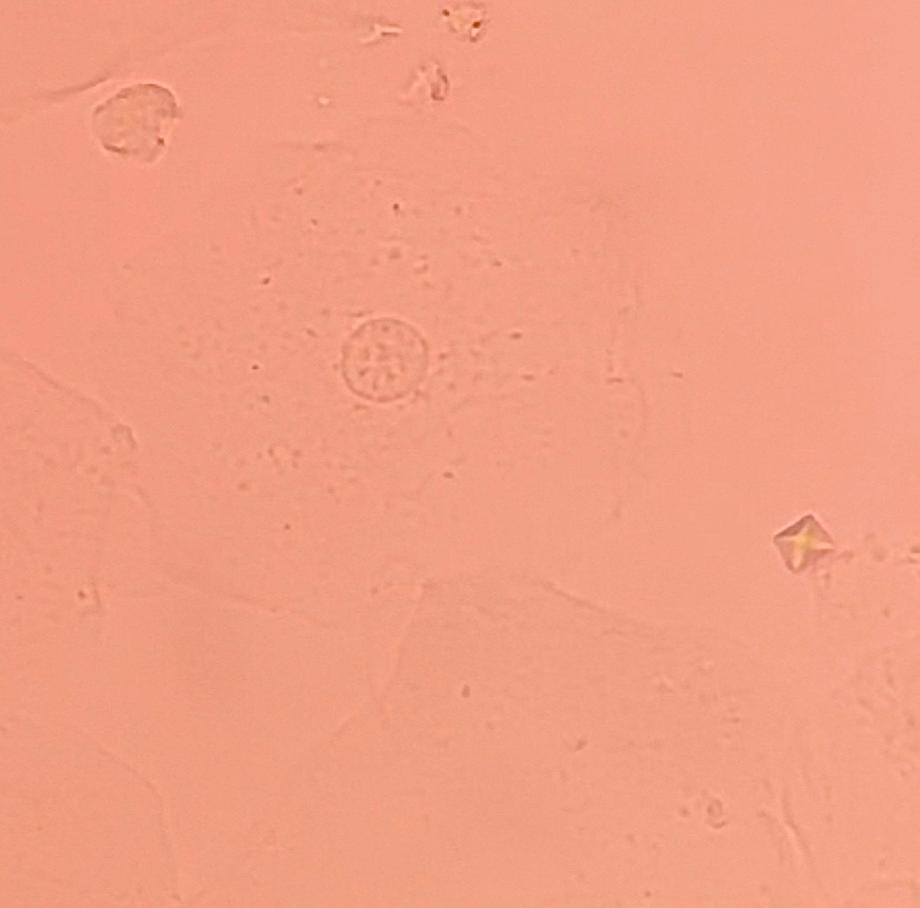

본문 시작 요 pH 측정 임상병리학과 392 2025-05-19 요 pH를 측정해본 후 산성뇨, 염기성뇨와 관련된 질병에 대해 알아보는 시간을 가졌습니다 목록 이전요시험지 테스트 다음 환자 검체를 이용한 요침사 검경 & 회식 만족도조사 만족도 조사 이 페이지에서 제공하는 정보에 대하여 만족하시나요? 매우만족 만족 보통 불만족 매우불만족